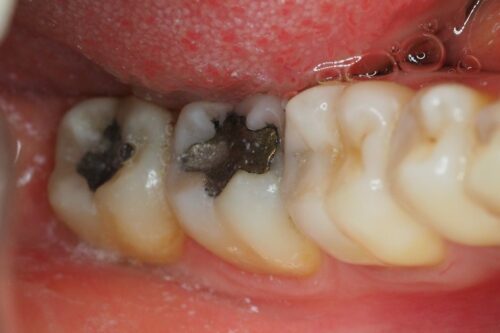

Pacjentka zgłosiła się na kolejną wizytę celem wymiany nieszczelnych wypełnień amalgamatowych. Na zdjęciu szóstka po odbudowie kompozytowej. Na życzenie Pacjentki leczenie zostało podzielone na etapy

Usunięto w odpowiedniej osłonie wypełnienie amalgamatowe oraz wykonano anatomiczną odbudowę powierzchni zgryzowej materiałem kompozytowym. Na kolejnej wizycie planowana jest wymiana wypełnienia w ósemce